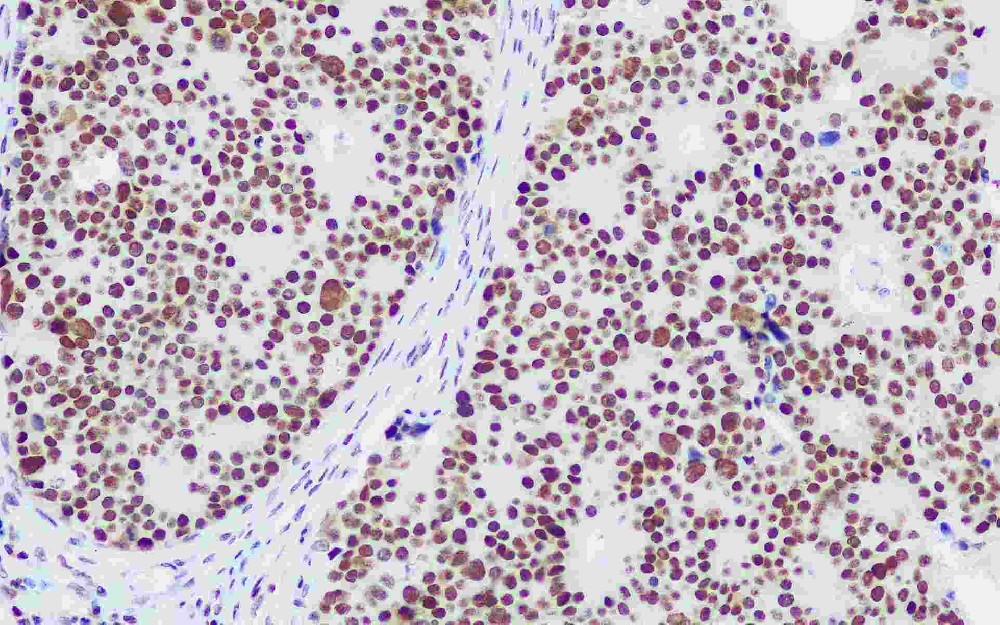

DNA錯配修復蛋白是一組核酶,在細胞增生期中DNA復制時參與錯配堿基的修復,這些蛋白與異常部位的DNA結(jié)合并將其移除。如果缺乏DNA錯配堿基修復酶,導致復制錯誤DNA的堆積在增生的細胞中不能被修復,這種現(xiàn)象稱為高頻度微衛(wèi)星不穩(wěn)定性,與之相對應(yīng)的是低頻度微衛(wèi)星不穩(wěn)定性和微衛(wèi)星穩(wěn)定。在人類DNA 錯配基因突變率高并與腫瘤相關(guān)的有MLH1(49%),MSH2(38%),MSH6(9%)和PMS2(2%)。DNA錯配修復蛋白缺陷和一些人類腫瘤有關(guān),比如遺傳性非息肉性結(jié)、直腸癌(HNPCC)。MLH1和MSH2突變者有超過70%發(fā)展為結(jié),直腸癌,50%發(fā)展為內(nèi)膜癌,但預(yù)后比低頻度微衛(wèi)星不穩(wěn)定性和微衛(wèi)星穩(wěn)定的患者好。與分子生物技術(shù)比較,免疫組織化學分析MMR簡單、便宜,多數(shù)實驗室可進行。所以,免疫組織化學檢測MLH1、MSH2、MSH6、PMS2被推薦為有家族遺傳性非息肉性結(jié)、直腸癌的人群的常規(guī)研究。